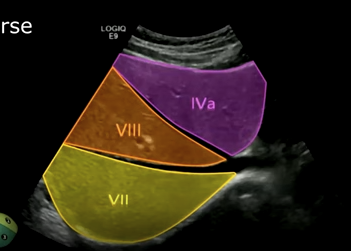

Superior segments of the liver: Segment two, segment four a, and segment eight.

Superior segment of the right lobe (transverse): Hepatic veins, segments four a, eight, and seven.

Middle hepatic vein separates four a from eight.

Right hepatic vein separates eight from segment seven.